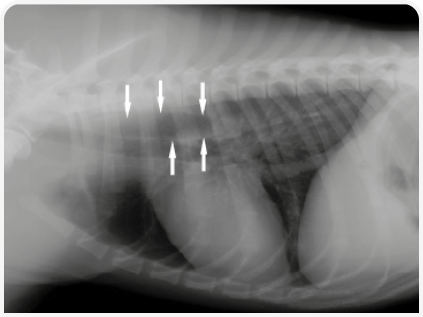

Кобель породы мопс в возрасте 11 месяцев поступил в ветеринарную клинику в связи с острой анорексией и регургитацией, которые развились за 3 дня до этого. Результаты клинического осмотра и исследования крови не выявили каких-либо существенных отклонений. При рентгенографическом исследовании грудной клетки было обнаружено затемнение в области дистального отдела пищевода, что указывало на наличие инородного тела, предположительно кости (Рисунок 1). Результаты эндоскопического исследования пищевода показали расширение пищевода в области краниального отверстия грудной клетки, а также внедрение кости в стенку пищевода краниальнее кардиального отверстия (Рисунок 2). Попытки извлечь инородное тело с помощью эндоскопии не принесли результата, хотя положение пациента меняли несколько раз. Впоследствии инородное тело сместилось в желудок. Результаты дальнейшего эндоскопического исследования не показали каких-либо патологических изменений в желудке, однако из-за тяжелых некротических язвенных поражений пищевода и возможного риска его перфорации через два дня была проведена гастротомия для извлечения кости. Затем в течение 10 дней проводилось лечение с введением омепразола, сукральфата, антибиотика и метилпреднизолона. Так как могла развиться послеоперационная стриктура, то в случае персистирования клинических симптомов было запланировано эндоскопическое исследование, однако выздоровление прошло без осложнений, и спустя год клиническое состояние собаки было удовлетворительным.